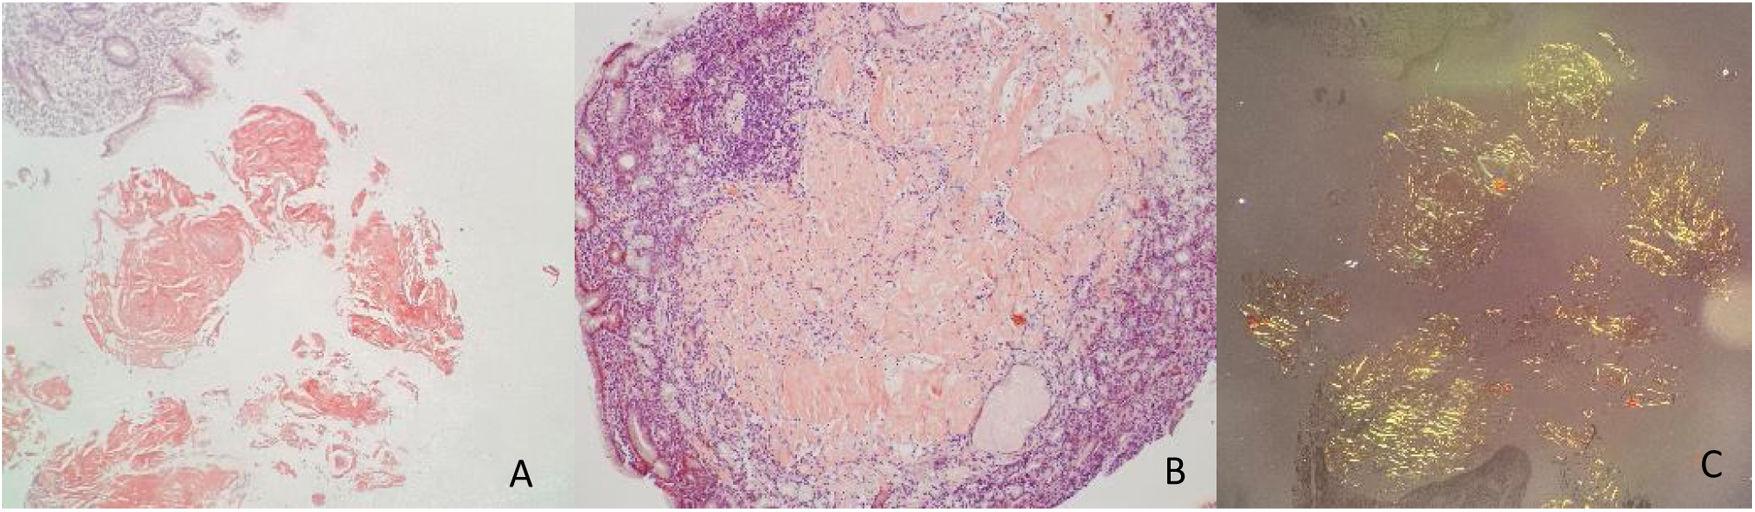

MALT lymphoma of the conjunctiva of both eyes a Initial examination Salmon Colored Lesions pityriasis rosea is a relatively mild skin disorder characterized by a salmon or pink colored, scaly rash. it is characterized by light flaking on the scalp that may spread to the hairline, retroauricular area, and eyebrows. the typical initial skin lesion of pityriasis rosea (pr), seen in more than 50% of patients, is a single pink macule. Salmon Colored Lesions.